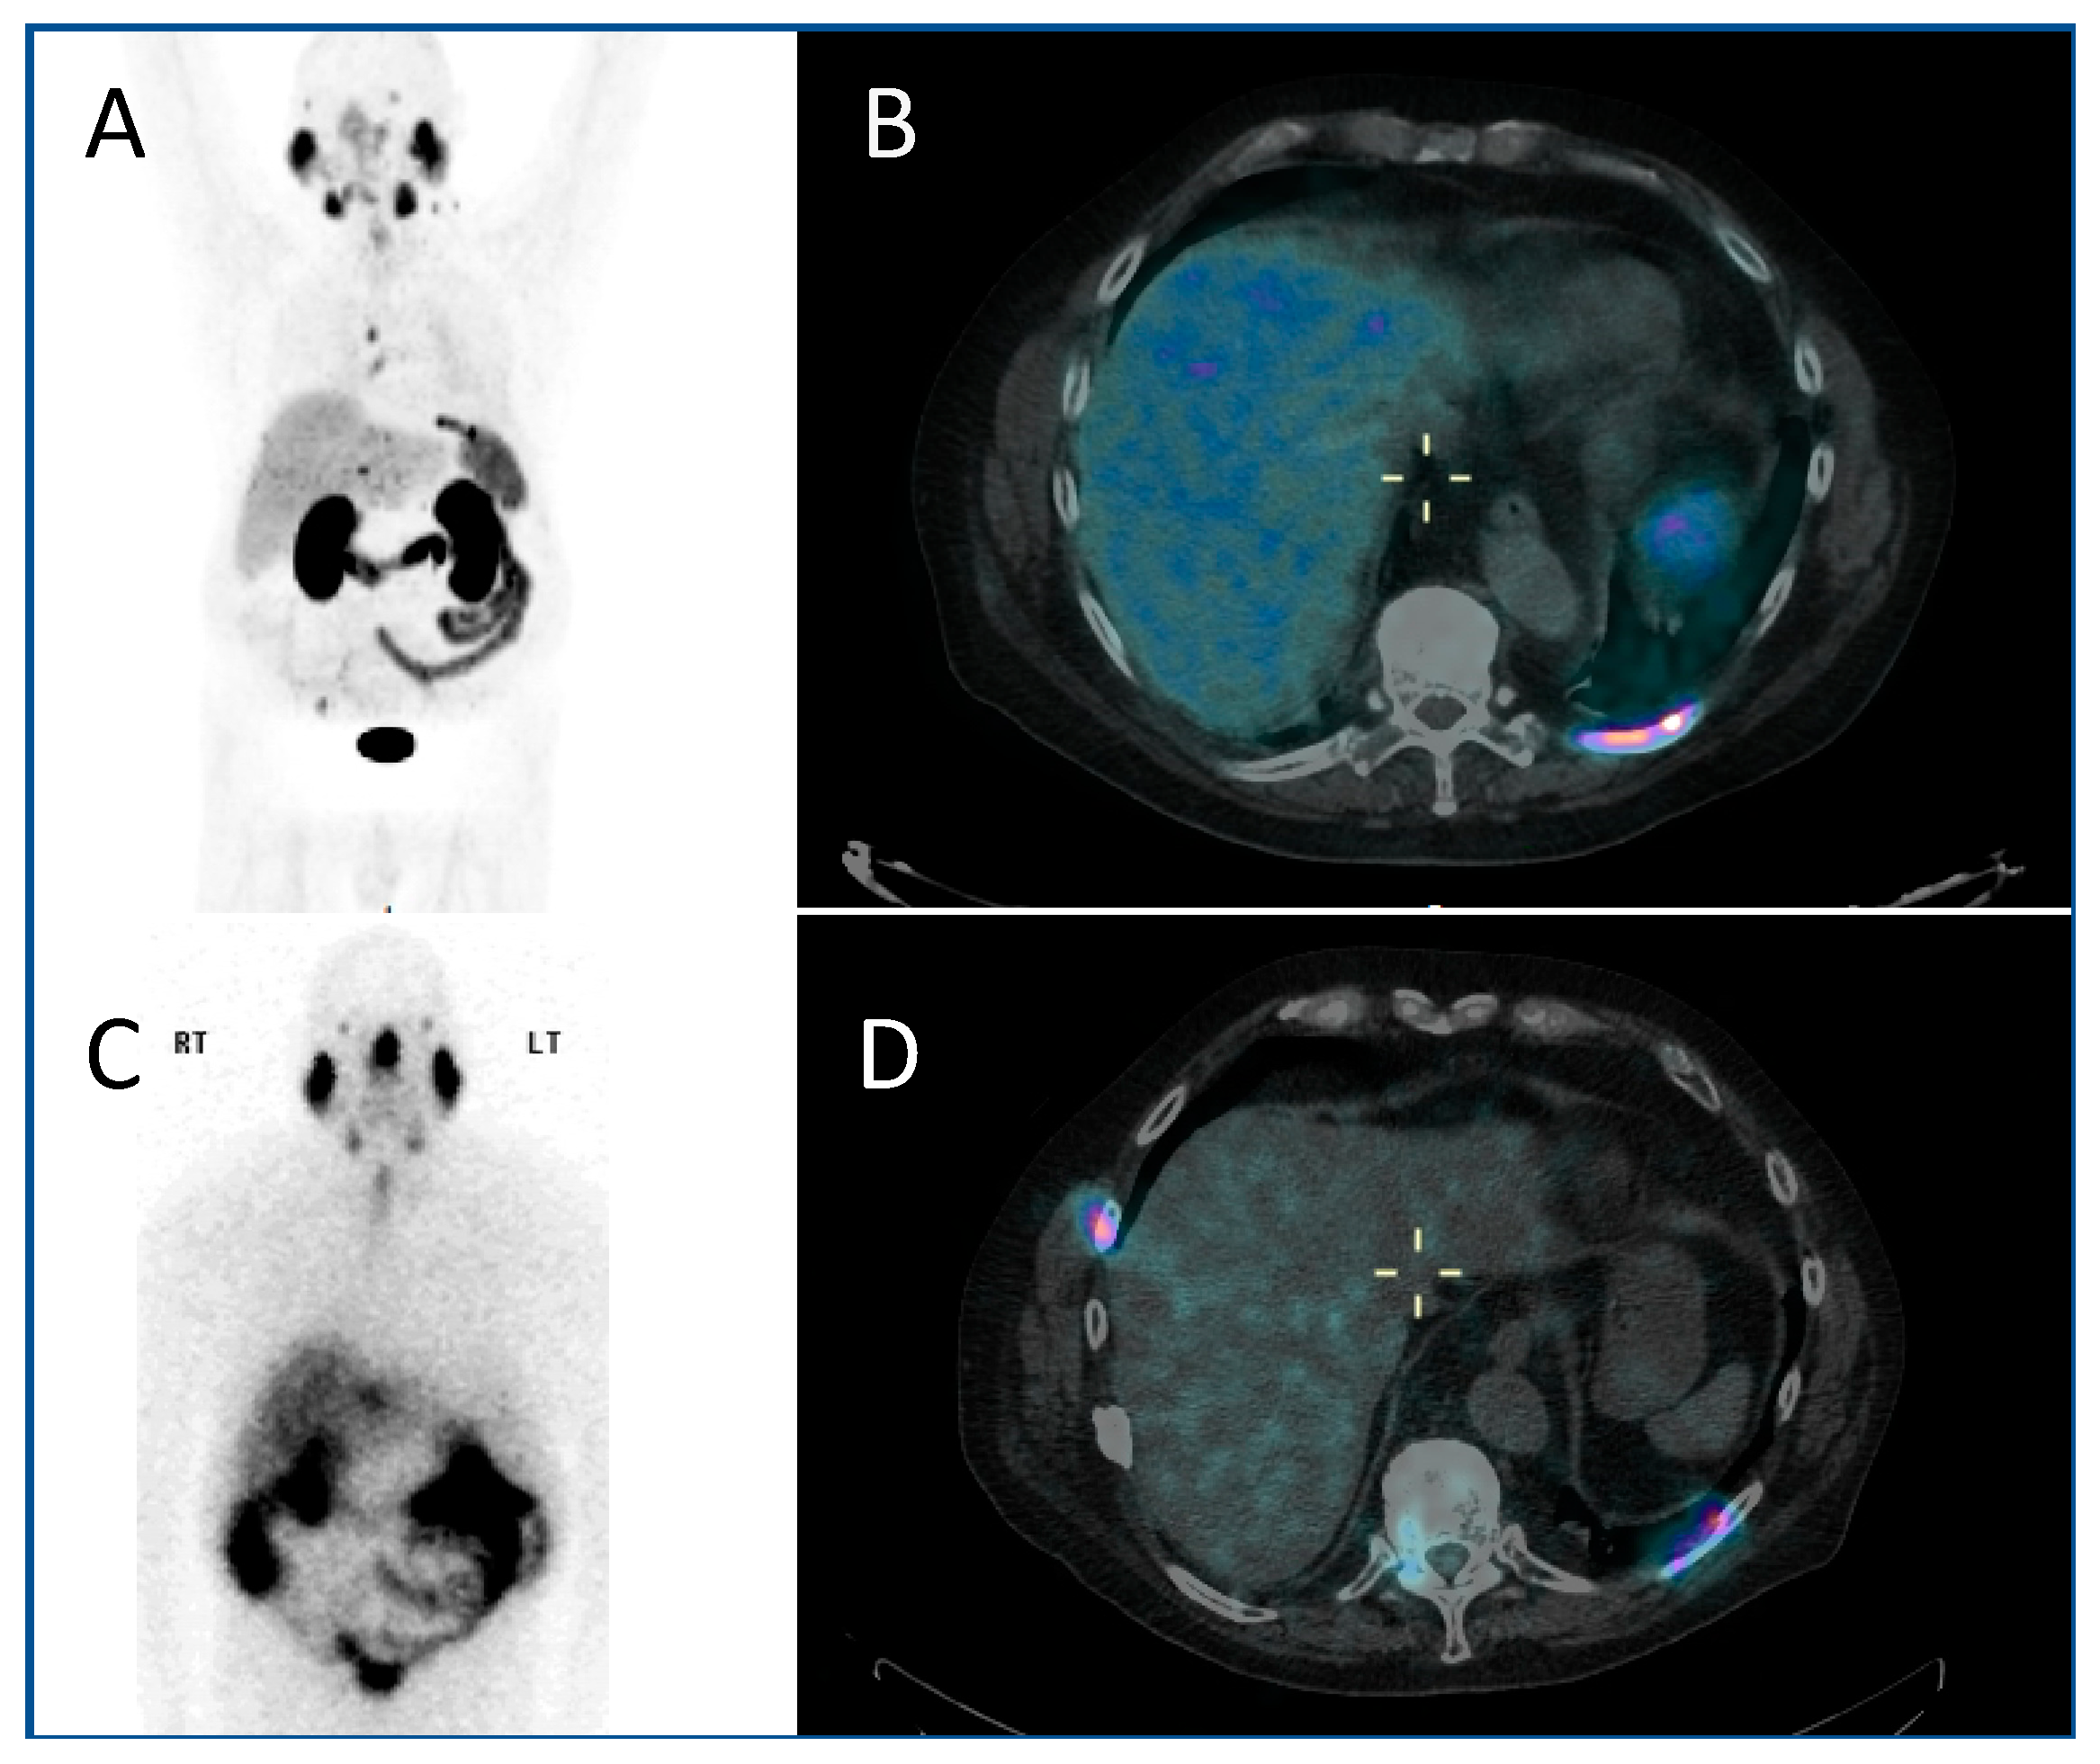

A similar approach is used with serial 111In-labelled anti-CD66 monoclonal antibody SPECT (single photon emission computed tomography) CT imaging (Figure 4) for dosimetry prior to 90Y anti-CD66 monoclonal antibody therapy, as an alternative to total body irradiation as conditioning prior to allogeneic bone marrow transplantation for relapsed leukaemia, to ensure that organ at risk doses are not exceeded [50].

Figure 4.

Dosimetry imaging with 111In-labelled anti-CD66 monoclonal antibody in a patient with relapsed leukaemia prior to 90Y anti-CD66 monoclonal therapy in an early phase trial [50]. (A) Anterior and (B) posterior whole-body planar scintigraphy views; (C) axial, (D) coronal and (E) sagittal fused SPECT CT views; and (F) SPECT maximum intensity projection image. These demonstrate avid uptake in areas of involved bone marrow.